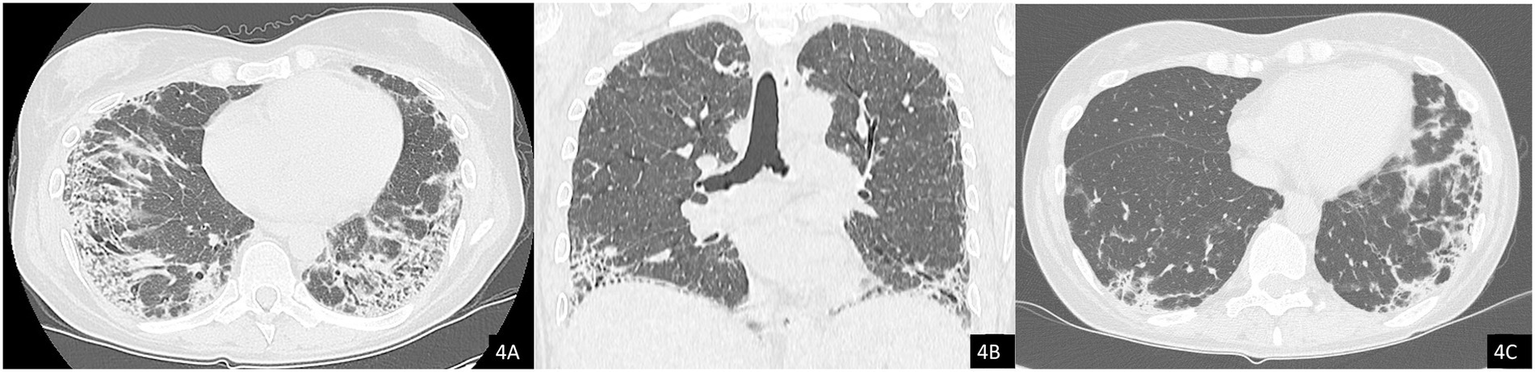

In October 2024, a Positron Emission Tomography (PET) scan conducted as part of her routine oncologic surveillance revealed findings suggestive of interstitial lung disease (ILD), spontaneous pneumomediastinum, and subcutaneous emphysema, initially without evident signs on physical examination. Subsequently, the emphysema progressively developed, with rhinolalia and subcutaneous emphysema extending to the neck. An urgent CT scan of the neck and chest confirmed a diagnosis of pneumocervicum, pneumomediastinum, pneumopericardium, and subcutaneous emphysema (Figures 3A,B). Following a pulmonology evaluation, hospitalization was deemed necessary for further management. A conservative approach was adopted following thoracic surgery consultation, and low-flow oxygen therapy was initiated. A bronchoscopy was performed to obtain microbiological samples and to identify any pulmonary lesions that could have contributed to the air formation in the mediastinum. The procedure, however, was negative for significant findings, but was complicated by pulmonary consolidation, which was treated with piperacillin-tazobactam and linezolid. An esophagogastroduodenoscopy was also performed, which ruled out the presence of an esophageal fistula. After a follow-up CT scan that demonstrated improvement in the pneumomediastinum and pneumocervicum, the patient was discharged.

Figure 3. Axial computed tomography (CT) images, lung window. (A) Evidence of pneumomediastinum and interstitial emphysema with dissection through the extrapleural spaces and soft tissues of the chest wall. (B) Axial image at the cervical level showing pneumocervicum. (C) Subsequent chest CT scan showing marked worsening of subcutaneous and mediastinal emphysema.

Subsequently, the patient was soon re-hospitalized as she experienced new episodes of acute rhinolalia and marked subcutaneous emphysema, extending from the chest to supraorbital region, with massive pneumomediastinum and pneumocervicum (Figure 3C). During this second hospitalization, two 28fr drainage segments were placed, resulting in significant air evacuation. The patient was then discharged on home oxygen therapy (2 L/min).